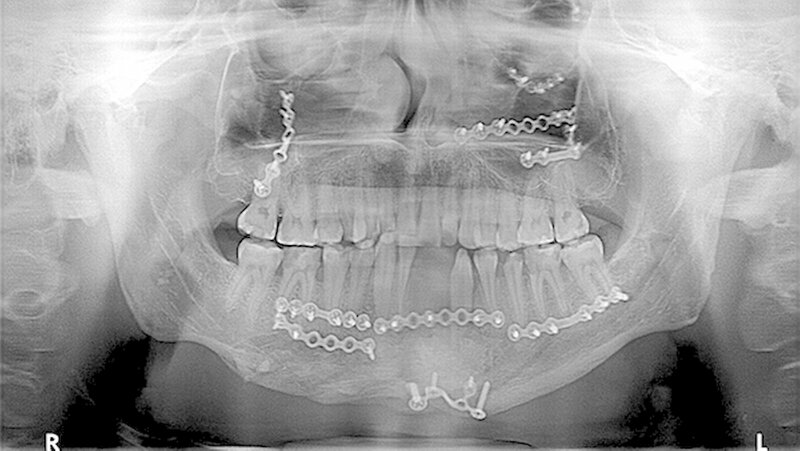

Vor der definitiven Fixierung der Prothesen wurden Dummys als Test eingesetzt, um eine optimale Positionierung der passgenauen finalen Prothesen zu erreichen (Abbildung 2 bis 9). Abbildung 10 a und 10b zeigen die postoperative Röntgenkontrolle.